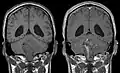

Les épendymomes supratentoriels (SE) représentent entre 40 % et 60 % des tumeurs intracrâniennes. Localisées au niveau supratentoriel, ces tumeurs apparaissent comme des grosseurs peu homogènes, présentant des zones kystiques, des calcifications mais également des zones hémorragiques et nécrosées.

Aspect radiologique à l’IRM en séquence T1 après injection de Gadolinium d’un épendymome supratentoriel, caractérisé par une lésion bien délimitée du lobe frontal gauche avec prise de contraste hétérogène et des zones de nécrose.